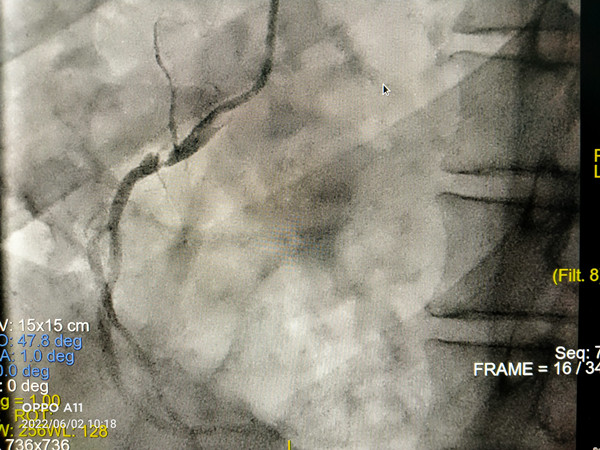

心血管病院成功开展TAVR+PCI一站式手术

近日,我院心血管病医院副主任韩振华、王新宏副主任医师的心脏瓣膜团队,成功为一名风湿性心脏病联合瓣膜病(主动脉瓣重度狭窄伴重度反流)合并冠脉严重病变患者实施一站式经导管主动脉瓣膜置换术(TAVR)+经皮冠状动脉支架植入术(...